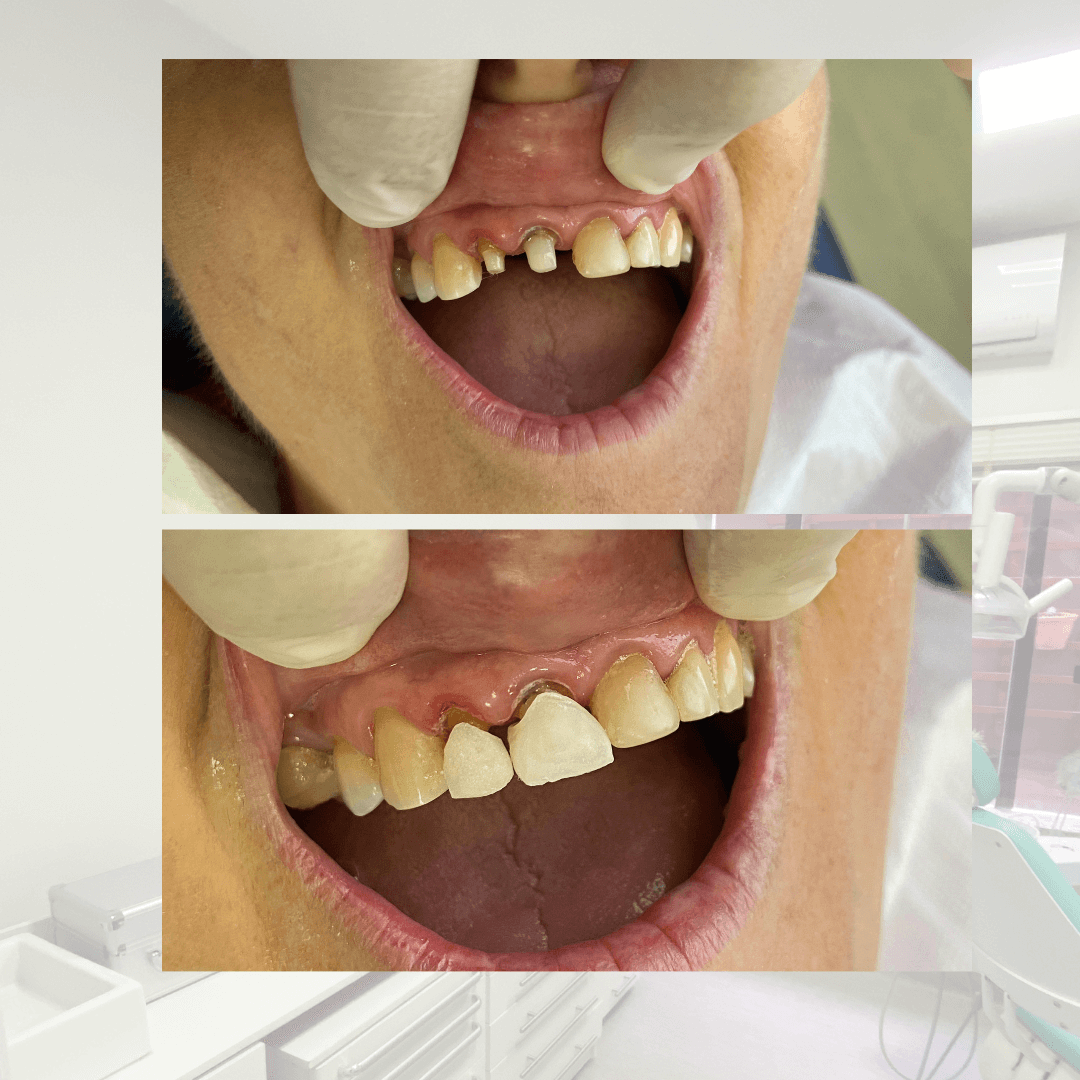

Tenho forte afinidade pela Endodontia, além de ampla experiência em reconstrução de dentes severamente destruídos e restaurações estéticas.

Meu foco é claro: salvar, restaurar e devolver confiança a cada sorriso com técnica, sensibilidade e precisão.